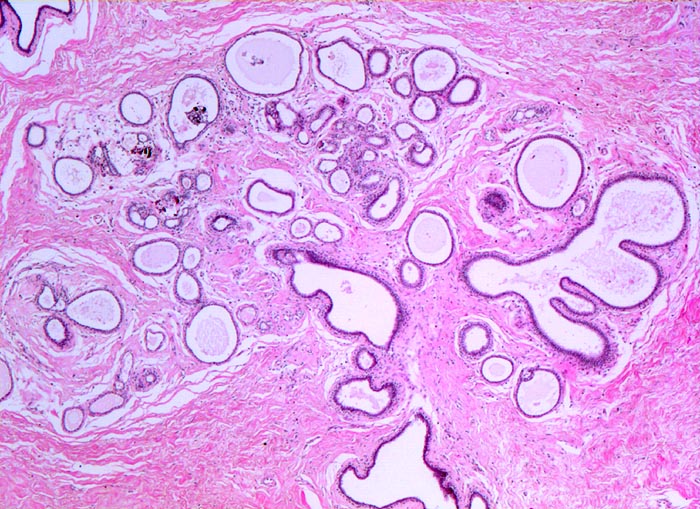

fibrös zystische Mastopathie mit intraduktalen Mikroverkalkungen

Mammagewebe mit fibrosiertem interlobulärem Stroma. Stroma der Drüsenläppchen ebenfalls fibrosiert (verdichtetes Kollagen). Die Ausführgänge sind teilweise erweitert und enthalten teilweise Mikrokalk.

Probeexzision wegen umschriebenen Mikroverkalkungen in der Screeningmammographie. Bei der Palpation lassen sich mehrere unscharf begrenzte derbe Knoten tasten.

320